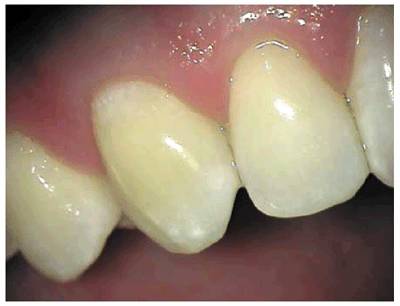

Figure 19-3: One week following crown preparation, the tooth structure was red, signifying extravasation of blood and the need for pulp extirpation.

Figure 19-33A: Pink crown preparation 1 week following instrumentation.

Figure 19-33B: Hemorrhagic pulp with extravasation of blood. (Photograph courtesy of Dr. Harold R. Stanley.)